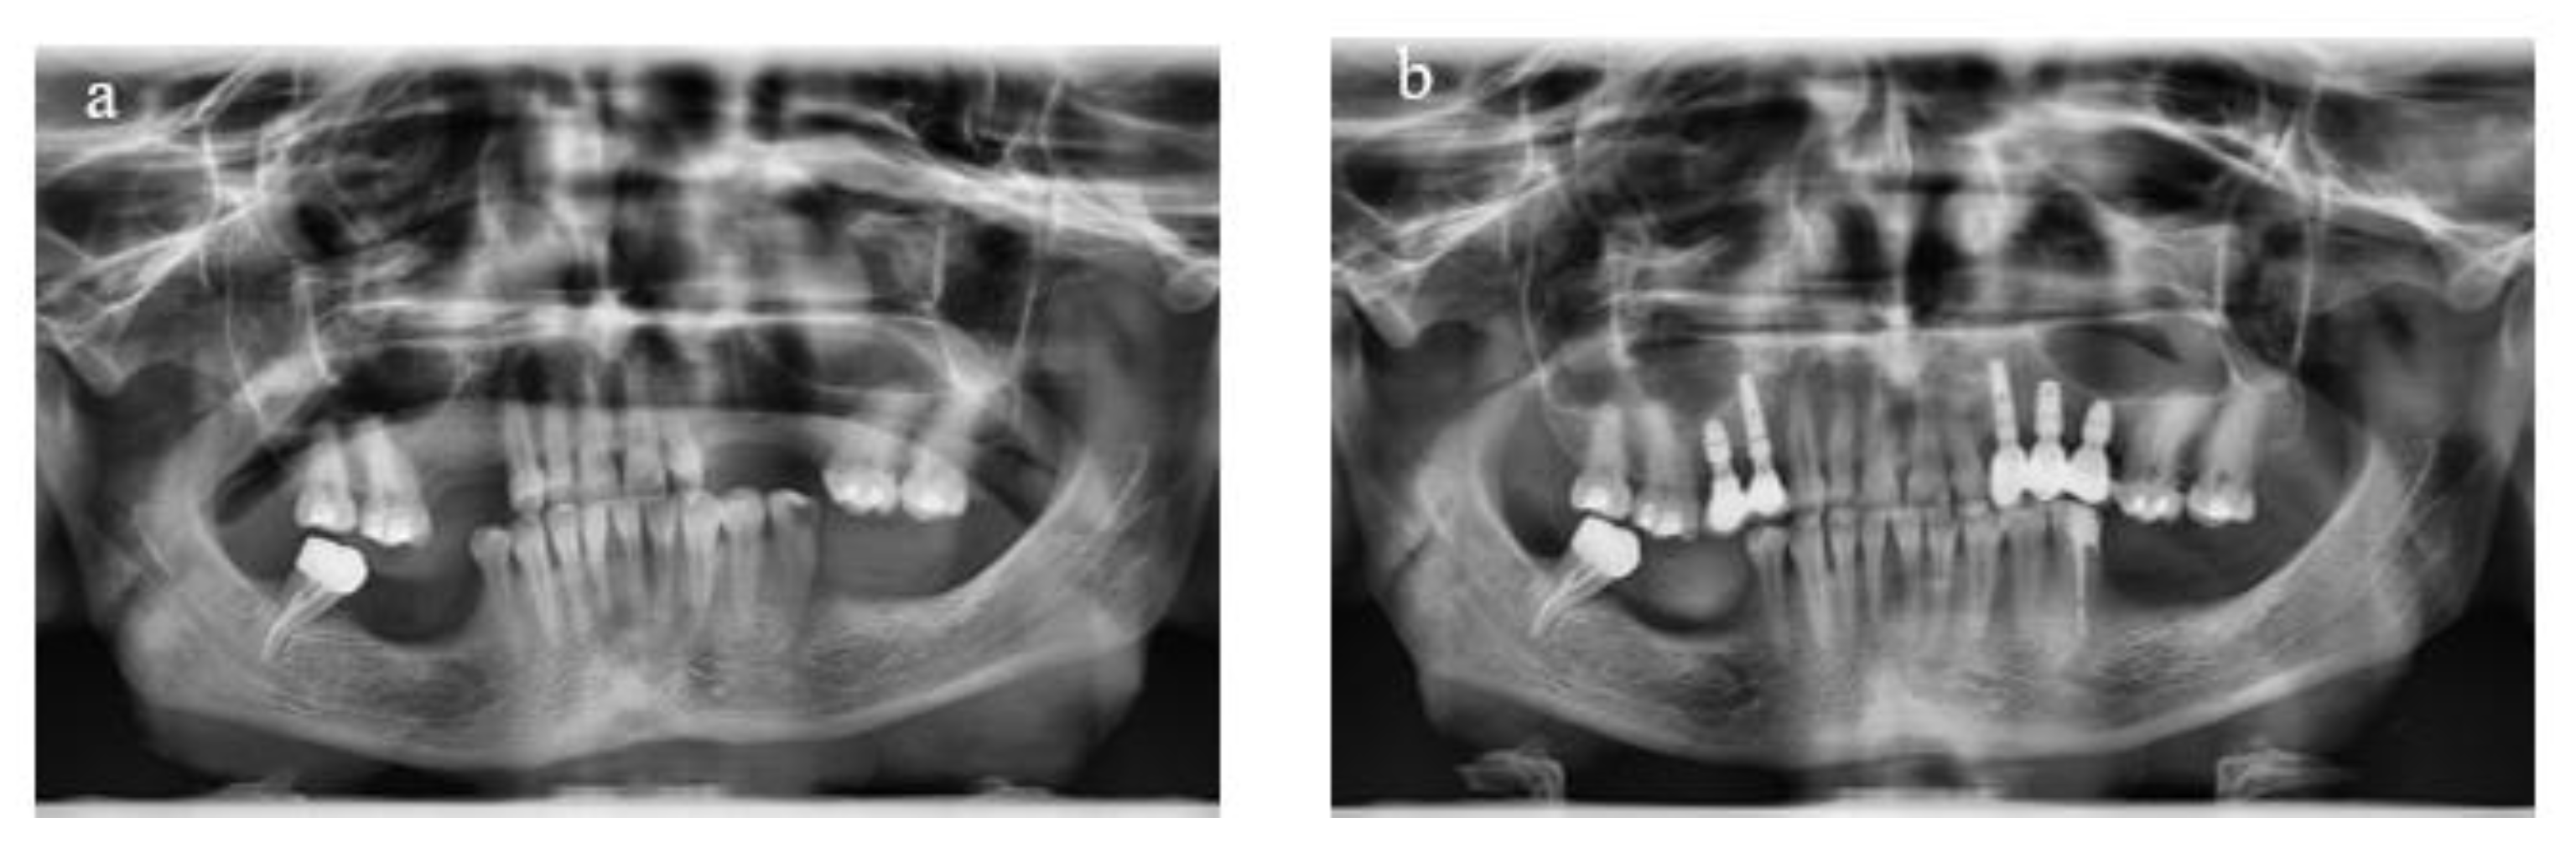

Treatment planning involved the use of diagnostic casts to assess intermaxillary relations, along with clinical photographs and panoramic radiographs (Figure 1). Cone beam computed tomography was utilized for most patients when necessary.

Figure 1.

Panoramic radiographs taken before the treatment to assist in diagnosis and treatment planning (a) and following implant placement and prosthesis delivery (b).